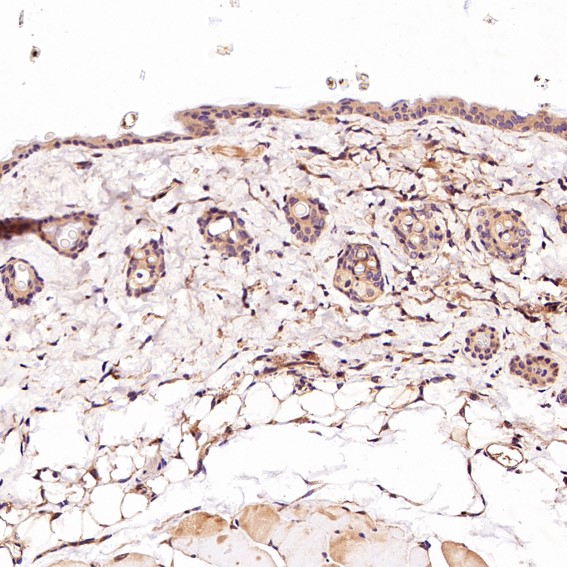

Immunohistochemical analysis of paraffin-embedded Mouse skin, using the Antibody.